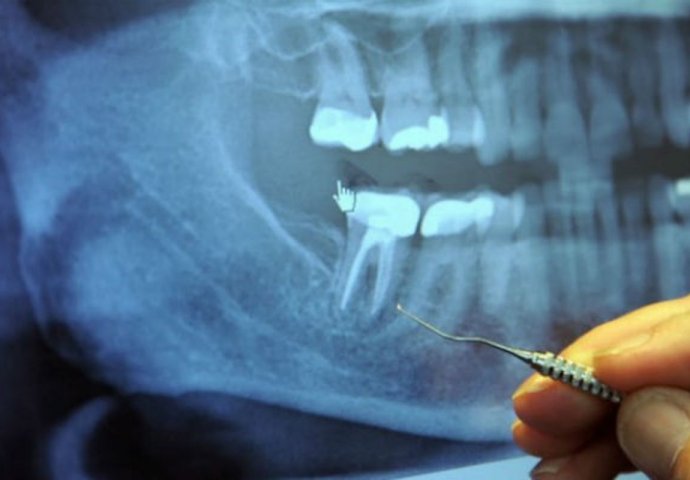

U sredini svakog zuba nalazi se zubna šupljina i u njoj pulpa, koja povezuje krvne sudove i nerve. Oko zubne šupljine se nalazi dentin, koji je sačinjen od živih ćelija koje luče tvrdu mineralnu supstancu. Spoljašnji dio zuba naziva se enamel i on okružuje dentin.

Korijeni svakog zuba dopiru do vilice i ostaju na svom mjestu zahvaljujući peridontalnom ligamentu. Stomatologe u školi uče da svaki zub ima 1-4 veća kanala. Međutim, postoji gomila kanala koja se uopšte ne pominje.

Svaki zub ima čitav lavirint sitnih cjevčica koje bi, kad bi se razmotale, bile dužine oko nekoliko kilometara. Veston Prajs je identifikovao 75 odvojenih pristupnih kanala u jednom centralnom sjekutiću.

Kad zubar izvede operaciju vađenja živaca, on probuši zub, a zatim ispuni šupljinu supstancom koja odsijeca dotok krvi do zuba, tako da ona više ne može da cirkuliše kroz zub. Međutim, lavirint cijevčica i dalje ostaje tamo, a bakterije, koje više nemaju svoj izvor hrane, kriju se u ovim tunelima gdje su bezbjedne od antibiotika i imune odbrane organizma.